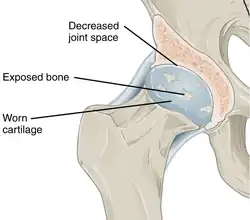

Annotated illustration of healthy hip joint

Healthy hip joint

Annotated illustration of hip joint with osteoarthritis

Hip joint with osteoarthritis[36]

While osteoarthritis is a degenerative joint disease that may cause gross cartilage loss and morphological damage to other joint tissues, more subtle biochemical changes occur in the earliest stages of osteoarthritis progression. The water content of healthy cartilage is finely balanced by compressive force driving water out and hydrostatic and osmotic pressure drawing water in.[37][38] Collagen fibres exert the compressive force, whereas the Gibbs–Donnan effect and cartilage proteoglycans create osmotic pressure which tends to draw water in.[38]

However, during the onset of osteoarthritis, the collagen matrix becomes more disorganized, and there is a decrease in proteoglycan content within cartilage. The breakdown of collagen fibers results in a net increase in water content.[39][40][41][42][43] This increase occurs because whilst there is an overall loss of proteoglycans (and thus a decreased osmotic pull),[40][44] it is outweighed by a loss of collagen.[38][44]

Other structures within the joint can also be affected.[45] The ligaments within the joint become thickened and fibrotic, and the menisci can become damaged and wear away.[46] Menisci can be completely absent by the time a person undergoes a joint replacement. New bone outgrowths, called "spurs" or osteophytes, can form on the margins of the joints, possibly in an attempt to improve the congruence of the articular cartilage surfaces in the absence of the menisci. The subchondral bone volume increases and becomes less mineralized (hypo mineralization).[47] All these changes can cause problems functioning. The pain in an osteoarthritic joint has been related to thickened synovium[48] and to subchondral bone lesions.[49]